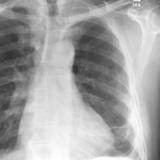

Microatelectasis (under debate)